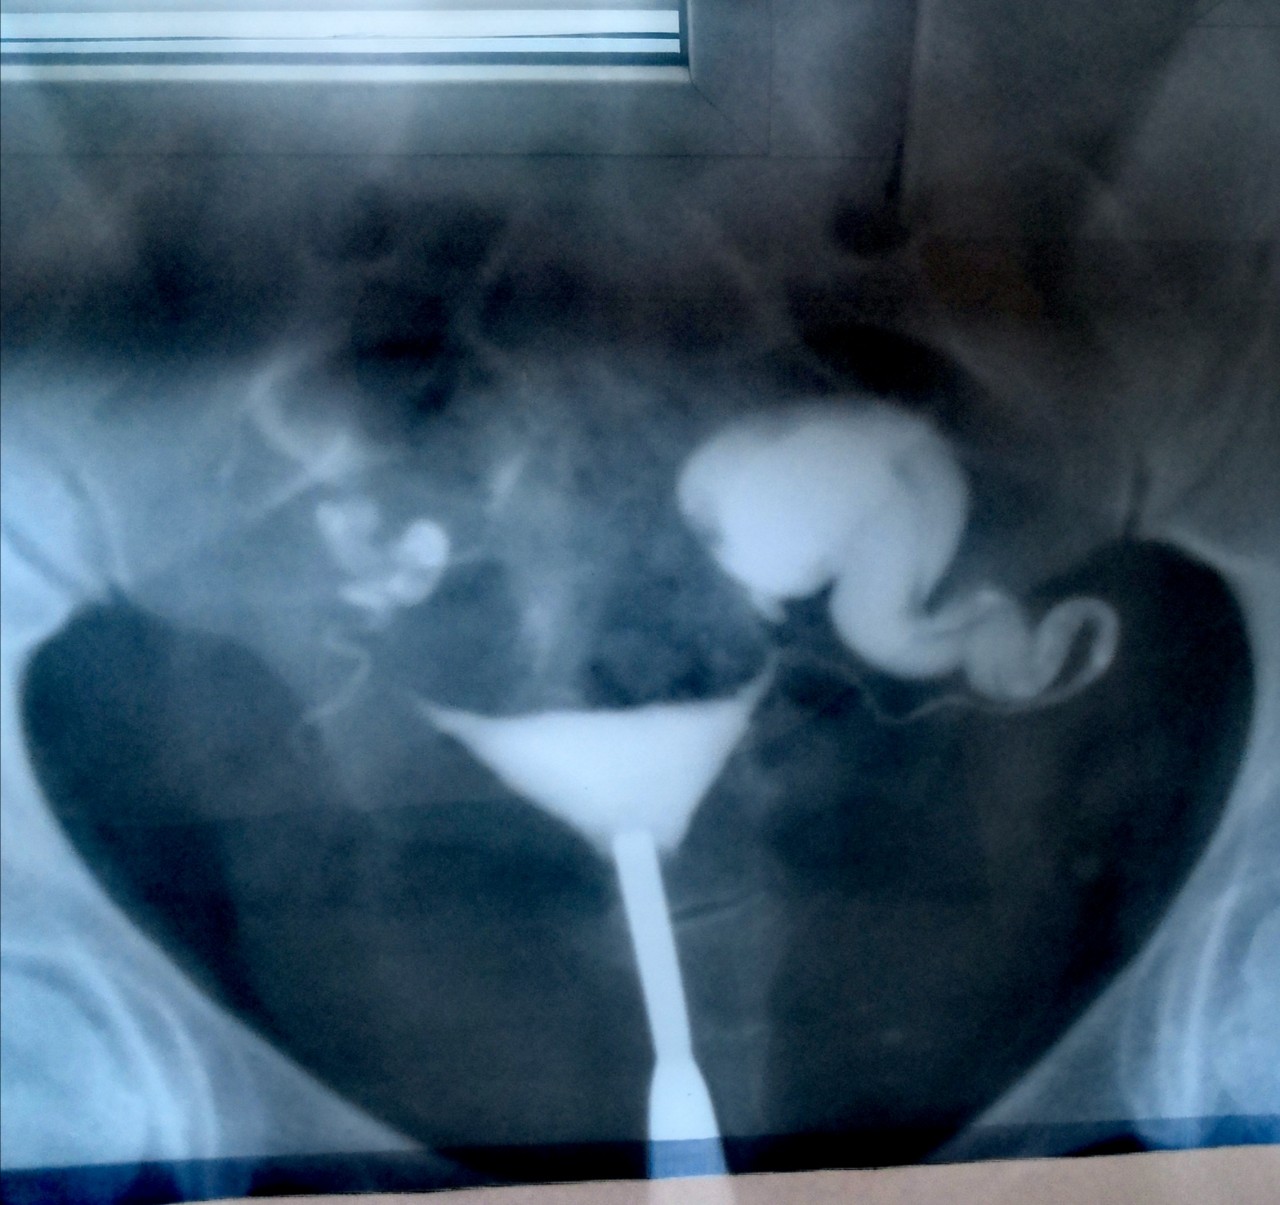

Гистеросальпингография: описание и фотографии